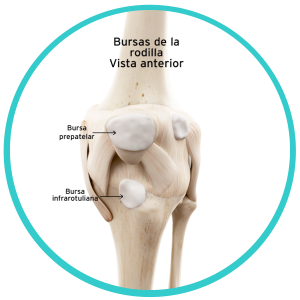

Las bursas o bolsas, son sacos llenos de líquido interpuestos entre dos huesos, entre huesos y músculos o tendones, o entre músculos y piel, para ayudar a disminuir la fricción que se genera con el movimiento de estas estructuras entre sí. Por ejemplo en la parte anterior de la rodilla tenemos dos bursas subcutáneas (pre-rotuliana e infra-rotuliana) que permiten que la piel se deslice fácilmente cuando movemos la rodilla.

Existen cuatro tipos de bursas:

• Sinoviales: La mayoría, son sacos muy delgados interpuestos entre huesos, músculos y tendones, formados por una membrana que contiene líquido sinovial que facilitan el deslizamiento de las estructuras entre sí.

• Adventicias: o accidentales, aparecen en prominencias óseas sometidas a presión o estrés constante. Un ejemplo típico es el llamado bunion en la cabeza del I metatarsiano cuando aparece el juanete o hallux valgus.

• Subcutáneas: Localizadas entre la piel y las prominencias óseas

• Submusculares: Localizadas entre los músculos y huesos o entre los propios músculos.

La rodilla tiene doce bursas algunas de ellas están comunicadas directamente con la articulación, así que cuando se inflama la rodilla, las bursas también se inflaman, causando una condición muy frecuente llamada Bursitis.